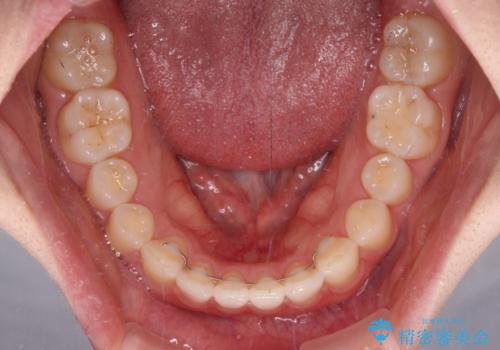

すきっ歯とオープンバイト インビザライン・ライトで改善

オープンバイトのため、奥歯に負担のかかる咬合状態であったので、矯正治療を提案したところ、希望をされました。

すきっ歯程度の軽度の歯列不正であったため、インビザライン・ライトにより咬合改善を行うこととしました。

オープンバイトやすきっ歯は、舌突出癖によりあっという間に後戻りをするため、矯正治療前からトレーニングを行っていただき、更には後戻り防止のワイヤーリテーナーを併用しています。